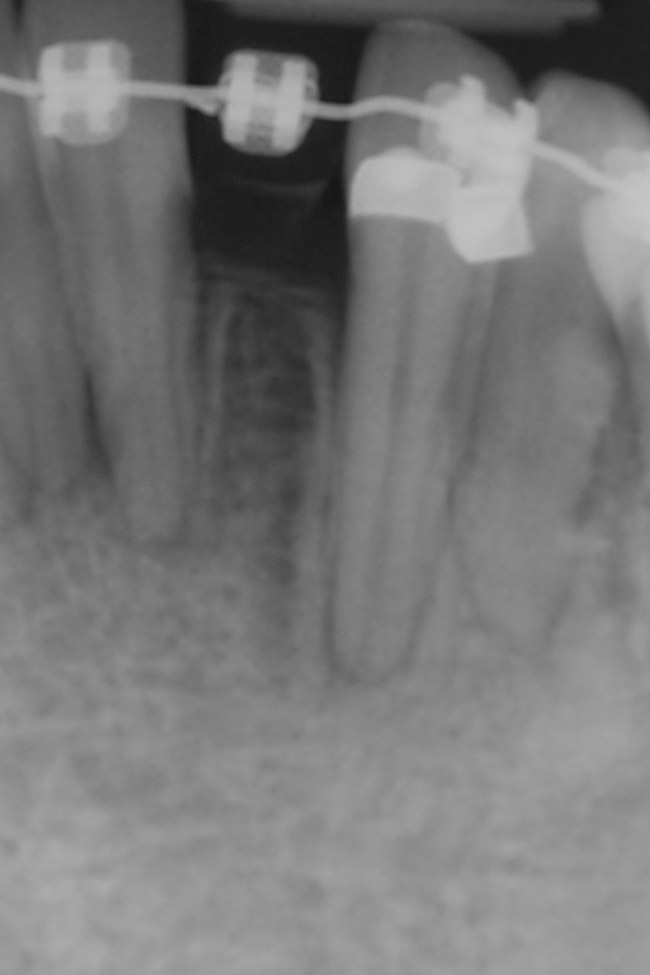

This treatment plan was elected with the premise to reevaluate treatment options during orthodontic tooth movement. Soft-tissue augmentation was initiated to correct the mucogingival defect in the area of teeth Nos. 21 and 22. A free gingival graft was performed to achieve an adequate band of attached and keratinized gingiva to resist potential stripping on the root surfaces of teeth Nos. 22 and 21 during orthodontic movement (Figure 8). Orthodontic movement then was initiated to site-develop position No. 23 for an implant (Figure 9 through Figure 11). Orthodontics also was used to idealize the patient’s occlusion and develop canine guidance to minimize occlusal load and maximize the redistribution of forces36-40 for protecting the future implant from deleterious forces. The space was opened around the peg lateral tooth No. 7, and the gingival levels were aligned for maxillary incisors. Bonding was performed to restore the length of teeth Nos. 8 through 10 and to bond the peg lateral to a normal tooth form, which allows the orthodontist to idealize the posterior occlusal scene and maintain canine guidance (Figure 12 through Figure 13).

Figure 10  Radiograph of orthodontic distraction osteogenesis.

Figure 10

Figure 11  Radiograph showing developed implant site of tooth No. 23.

Figure 11